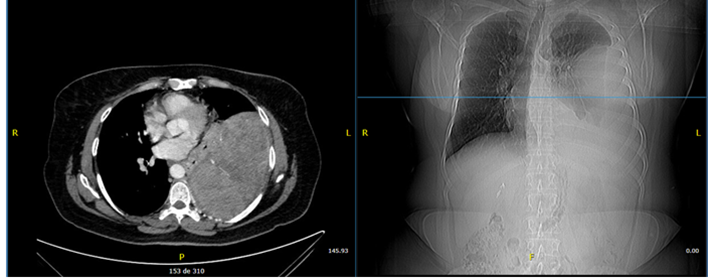

A 53-year-old female patient presented with a history of hypothyroidism treated with levothyroxine 100 mcg daily and stage IA2 cervical cancer treated with radical hysterectomy in 2005. There was no known family history of cancer. Denied smoking or exposure to environmental toxins. She presented to the Pneumology Department in May 2019 with a nonproductive cough lasting more than three months and progressive dyspnea. Initial physical examination revealed a respiratory rate of 22 rpm, oxygen saturation of 95% on room air, hypoventilation in the left lung base on pulmonary auscultation, and dullness to percussion in the left basal region. Tumor marker results were as follows: CYFRA 21-1: 1.85 ng/ml; NSE: 19.51 ng/ml. Pulmonary function tests evidenced a moderate restrictive pattern with no response to bronchodilators. Contrast-enhanced chest CT scan showed a heterogeneous extrapulmonary mass measuring 12.8 x 15.3 cm with a broad base on the left parietal pleura and no adenomegaly (Figure 1).

Figure 1

Contrast-enhanced chest CT scan. Left extrapulmonary heterogeneous lesion with an obtuse angle, which measures 12.8 x 15.3 cm.

Paciente femenina de 53 años con antecedentes de hipotiroidismo en tratamiento con levotiroxina 100 mcg/día y cáncer de cuello uterino estadio IA2 tratado mediante histerectomía radical en el 2005. Sin antecedentes familiares oncológicos conocidos. Niega hábito tabáquico o exposición a tóxicos ambientales. Consulta al departamento de Neumología en mayo del 2019 por tos no productiva de más de tres meses de evolución y disnea progresiva. En el examen físico inicial presentó frecuencia respiratoria de 22 rpm, saturación de oxígeno 95 % a aire ambiente; en la auscultación pulmonar, hipoventilación en base pulmonar izquierda y percusión mate en región basal izquierda. Resultados de marcadores tumorales: Fragmentos de citoqueratina 19 (CYFRA 21-1): 1,85 ng/ml; Enolasa Neuronal Específica (NSE): 19,51 ng/ml. Las pruebas de función pulmonar reportaron patrón restrictivo moderado sin respuesta a broncodilatador. La tomografía torácica con contraste reportó una masa extrapulmonar heterogénea, de 12,8 × 15,3 cm, con base amplia en pleura parietal izquierda, no adenomegalias (Figura 1).

Figura 1

Tomografía contrastada de tórax. Lesión heterogénea extrapulmonar izquierda de ángulo obtuso que mide 12,8 × 15,3 cm.